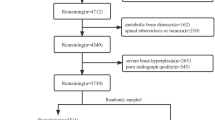

Analyzing spinal curvatures manually is time-consuming and tedious for clinicians, and intra-observer and inter-observer variability can affect manual measurements. In this study, we developed and evaluated the performance of an automated deep learning–based computer-aided diagnosis (CAD) tool for measuring the sagittal alignment of the spine from X-ray images. The CAD system proposed here performs two functions: deep learning–based lateral spine segmentation and automatic analysis of thoracic kyphosis and lumbar lordosis angles. We utilized 322 datasets with data augmentation for learning and fivefold cross-validation. The segmentation model was based on U-Net, which has multiple applications in medical image processing. Here, we utilized parameter equations and trigonometric functions to design spinal angle measurement algorithms. The kyphosis (T4–T12) and lordosis angle (L1–S1, L1–L5) were automatically measured to help diagnose kyphosis and lordosis. The segmentation model had precision, sensitivity, and dice similarity coefficient values of 90.53 ± 4.61%, 89.53 ± 1.8%, and 90.22 ± 0.62%, respectively. The performance of the CAD algorithm was also verified with the Pearson correlation, Bland–Altman, and intra-class correlation coefficient (ICC) analysis. The proposed angle measurement algorithm exhibited high similarity and reliability during verification. Therefore, CAD can help clinicians in reaching a diagnosis by analyzing the sagittal spinal curvatures while reducing observer-based variability and the required time or effort.